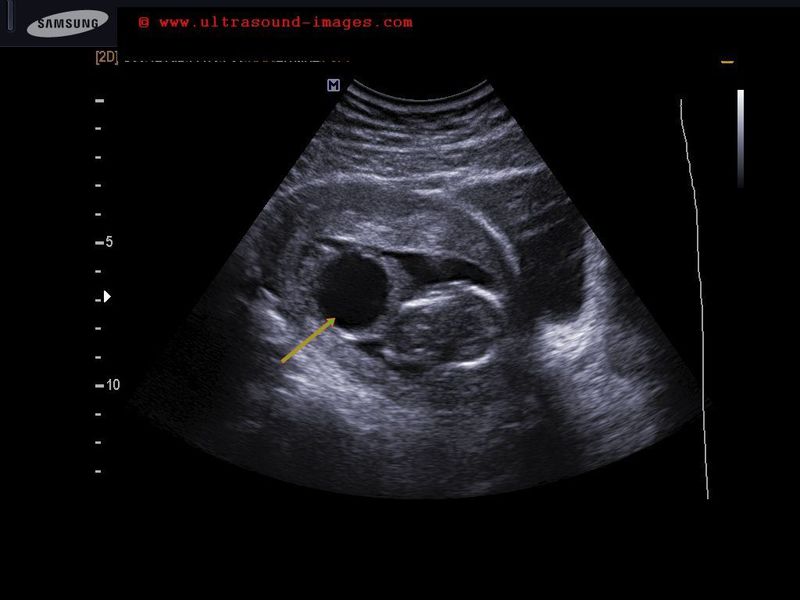

A rare case of ureterocele detected sonographically in 3rd trimester fetus Sonography of the fetal urinary bladder, shows a sac like structure (arrow) in the region of the distal end of the fetal left ureter. This ultrasound image suggests fetal ureterocele. Ureterocele is often seen in adults, but very rarely in a fetus. It is caused by defect during in embryogenesis of the fetal ureter. Ultrasound image is courtesy of Dr. Latha Natarajan, India.